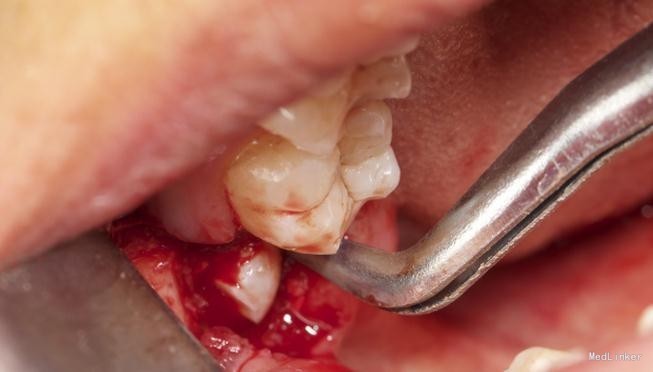

左下8水平阻生拔除

患者,男,25岁,要求拔除左下颌水平阻生牙齿,平素体质一般,无药物、食物过敏史,无高血压、心脏病等系统病史

拔除术